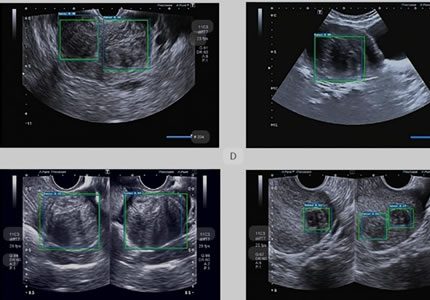

Routine & Diagnostic Gynaecological Scans

Symptom-Based & Condition-Specific Scans